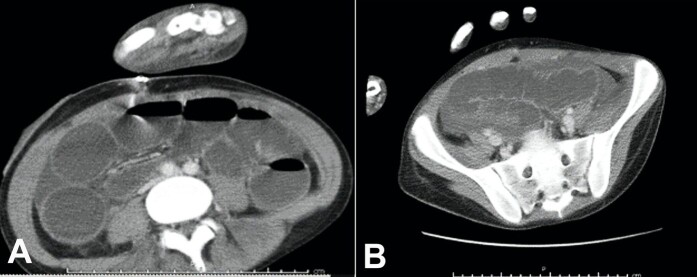

艰难梭菌感染(CDI)是美国数百万医院感染的罪魁祸首。因此,成功降低其发病率的项目为医疗保健系统节省了成本。毒性巨结肠和穿孔是死亡率增加的两个最重要的并发症。我们报告一名23岁的养老院居民因发烧,咳嗽和绿色痰而住院。抗生素治疗3天后,患者出现腹胀、腹泻和呕吐,并行全结肠切除术。结肠扩张至最大11cm,黏膜明显水肿,假膜呈黄色。粪便定量PCR检测艰难梭菌毒素B基因。虽然对于抗生素治疗和CDI之间的所需间隔时间没有共识,但在开始抗生素治疗后3天出现的时间比大多数建议的范围要早。

Clostridioidesdifficile infection (CDI) is the culprit of millions of nosocomial infections in the United States. Programs that successfully decrease its incidence, therefore, render cost savings for the healthcare system. Toxic megacolon and perforation are two of the most significant complications with increased mortality rates. We report a 23-year-old nursing home resident hospitalized for fever, cough, and green sputum. After 3 days of antibiotic therapy, he developed abdominal distension, diarrhea, and vomiting and underwent a total colectomy. The colon was dilated to a maximum of 11 cm with markedly edematous mucosa and yellow pseudomembranes. Qualitative PCR of the stool detected Clostridioides difficile toxin B gene. While there is no consensus for the required interval between antibiotic treatment and CDI, this presentation 3 days after starting the antibiotic therapy is earlier than most proposed ranges.